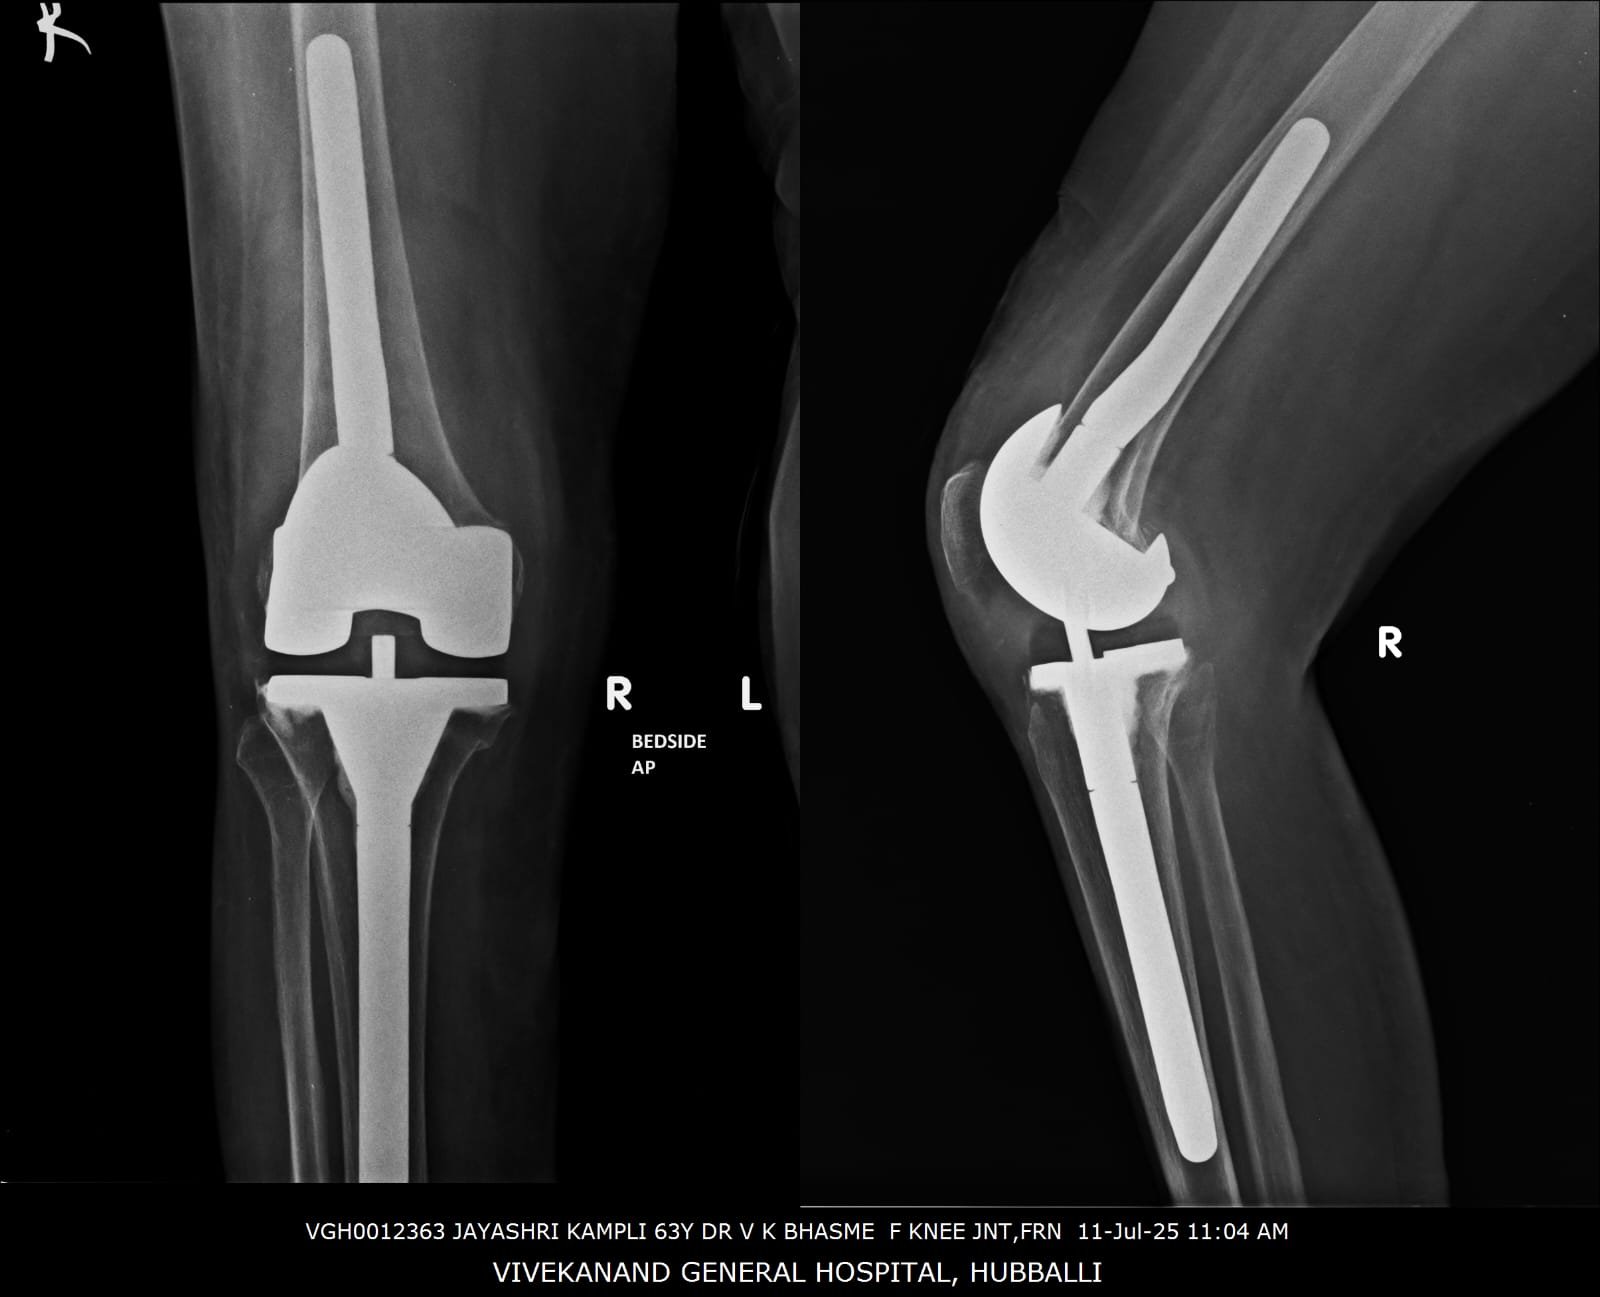

68 years lady was not walking for 5 years 8 months